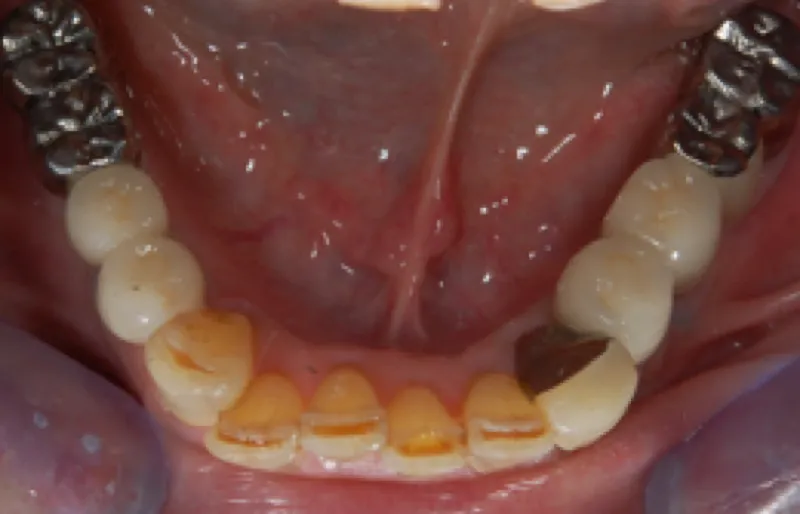

70代男性「違和感があって入れ歯が使えない」失った下の左右奥歯を、人工歯根を利用した「インプラント治療」で補い、しっかり噛めるようになった症例

拝見したところ、下の両側の奥歯(第1小臼歯/4番〜第2大臼歯/7番)が欠損しており、前歯でしか物が噛めない状態でした。 取り外し式の入れ歯をご使用されていましたが、違和感があるご様子で、装着すると吐き気が出てしまっていました。